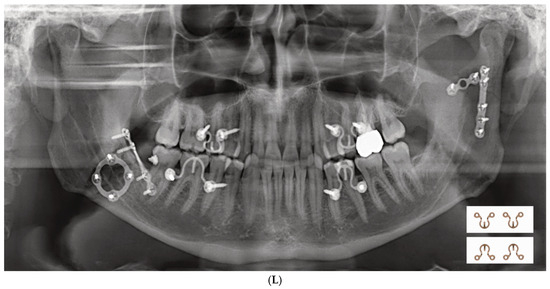

3.1. Matrix Wave Plate—Segmentation and Malleability

3.2. Matrix WaveTM Plate MMF System—Mode of Application